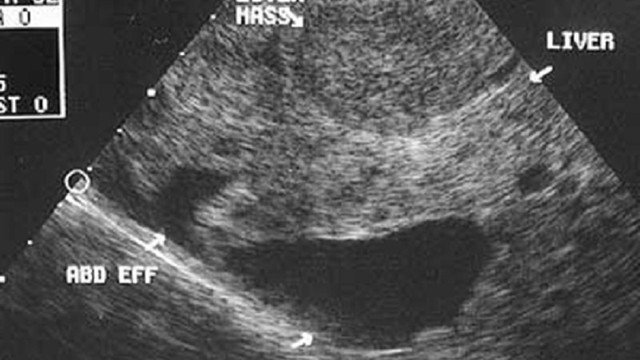

Ung thư gan là một trong những loại ung thư nguy hiểm với tỷ lệ tử vong cao, phần lớn do việc chẩn đoán muộn khi bệnh đã tiến triển nặng. Điều này khiến nhiều người đặt câu hỏi: "Siêu âm có phát hiện ung thư gan không?". Qua những thông tin dưới đây, bạn sẽ hiểu rõ hơn về tầm quan trọng của việc tầm soát ung thư gan, đặc biệt đối với các nhóm nguy cơ cao.

Ung thư gan là một trong những bệnh lý ác tính phổ biến và nguy hiểm, với tỷ lệ tử vong cao trên toàn thế giới. Hình ảnh ung thư gan nguyên phát thường xuất hiện với các khối u trong gan, trong khi ung thư gan thứ phát chủ yếu là sự di căn từ các cơ quan khác. Cùng tìm hiểu hình ảnh điển hình của ung thư gan nguyên phát và thứ phát trong bài viết hôm nay nhé.